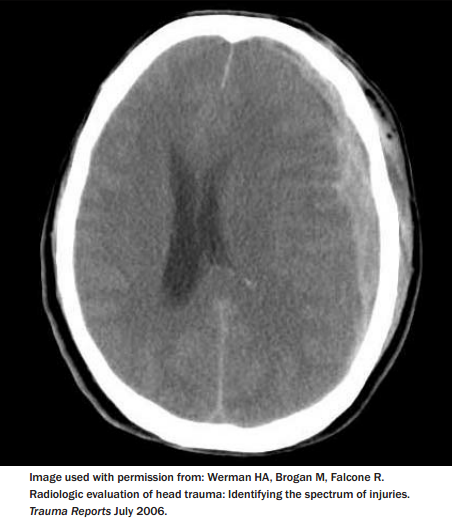

In contrast with alpine skiing, snowboarding is associated with more upper extremity injuries (most commonly wrist injuries), shoulder injuries, ankle injuries, spinal injuries, and head injuries.14-18 (See Table 1.) Head injuries make up nearly one-quarter of snowboarding injuries and are more likely to be seen in male participants. Head injuries account for nearly one-half of the snowboarding injury transfers to trauma centers.1,3 Most of these head injuries occur from loss of the board edge and falling on mild to moderate slopes.1 Snowboarders are more likely to suffer from intracranial hemorrhage requiring craniotomy than skiers, and more frequently require longer rehabilitation and ongoing care. Interestingly, snowboarders are more likely to sustain a subdural hematoma as compared to skiers, who are more likely to have a skull fracture.1 (See Figure for a CT image of subdural hematoma.) Fortunately, most head injuries seen are mild, and the most common diagnosis is concussion. Table 2 shows the incidence of injury to various regions of the brain.19 A growing use of helmets has been associated with a decrease in the number of head injuries and may change some of these patterns of injury.20,21

Figure: CT of Subdural Hematoma